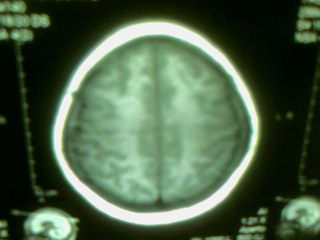

标题: MRI2125:女 45岁 头疼头晕3个月 [打印本页]

标题: MRI2125:女 45岁 头疼头晕3个月

1)考虑第四脑室脉络膜丛乳头状瘤,不排除室管膜瘤。2)阻塞性脑积水。

考虑 第四脑室室管膜瘤或脉络膜丛乳头状瘤伴梗阻性脑积水。

1)考虑第四脑室室管膜瘤,不排除脉络膜丛乳头状瘤。2)阻塞性脑积水。